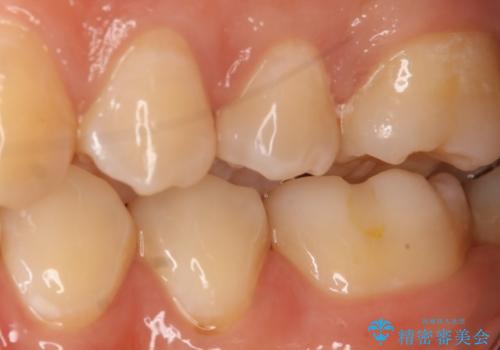

- 左上5番の虫歯治療を主訴に来院された患者様です。

セラミックでの治療を希望されたので形態・切削量を考慮しセラミックインレーでの治療を選択しました。

隣り合っている面(隣接面)は清掃がしづらく虫歯になりやすい場所です。

また、形態の再現が難しいのでインレーなどの補綴物での治療が第一選択となることが多いです。